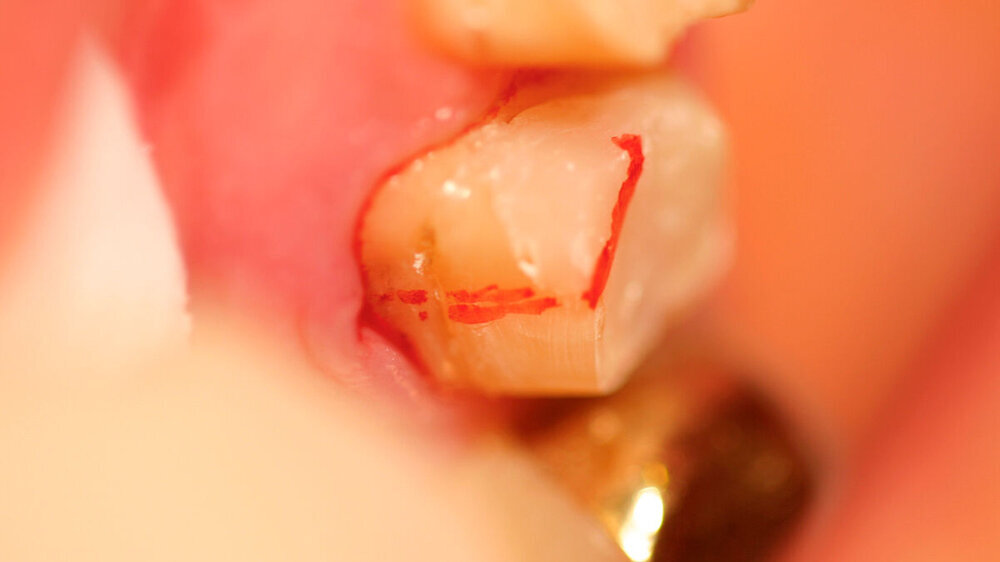

Nach der Anästhesie erfolgt bei einer beabsichtigten Entfernung einer der beiden bukkalen Wurzeln ein Ertasten der vestibulären Furkation. Wir halten es für ratsam, von der Furkation nach okklusal eine deutlich sichtbare Markierung mit einem wasserfesten Stift anzuzeichnen und diese Linie okklusal halbkreisförmig um die zu entfernende Wurzel zu verlängern. Das erleichtert die Orientierung beim Absetzen des zu entfernenden Zahnanteils. (Abbildung 1a).

Anschließend verwenden wir eine Lindemannfräse (H162SL, Firma Komet Dental, Lemgo) in einem Schnelllaufwinkelstück und trennen die Wurzel mitsamt des Kronenanteils vorsichtig entlang der zuvor angezeichneten Linie ab. Um den zu erhaltenden Zahnanteil nicht unbeabsichtigt mit der Fräse zu beschädigen, bleibt die Orientierungslinie zunächst unangetastet (Abbildung 1b).